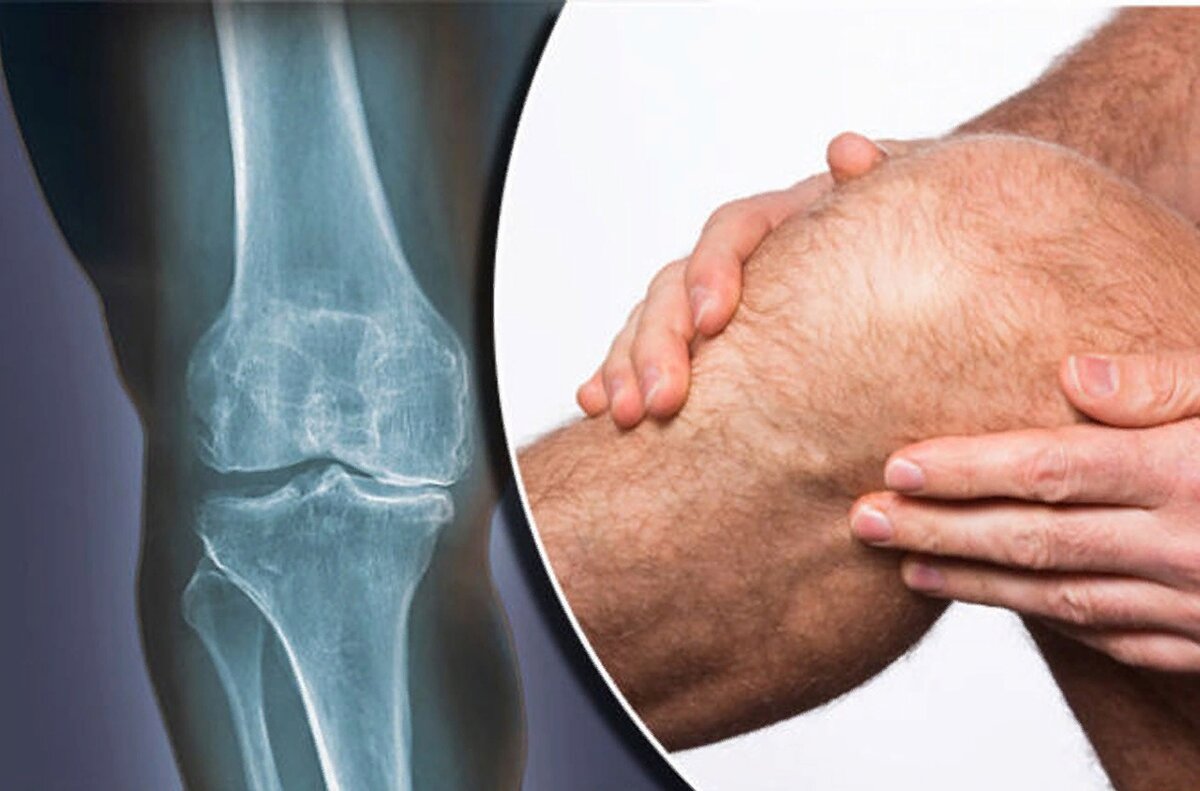

Остеоартрит (остеоартроз). Что нового?

Остеоартрит - хроническое дегенеративное заболевание, которое поражает все ткани сустава (хрящ, кость, синовиальная оболочка, капсула, околосуставные ткани).

Локальный воспалительный процесс, возникший в результате микроповреждения тканей сустава из-за перегрузки, травмы, метаболических проблем и других причин. С течением времени воспаление все сильнее повреждает ткани сустава, доходя до видимых деформаций.